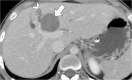

Hydatid disease is a worldwide zoonosis endemic in many countries. Liver echinococcosis accounts for 60-75% of cases and may be responsible for a wide spectrum of complications in about one third of patients. Some of these complications are potentially life-threatening and require prompt diagnosis and urgent intervention. In this article, we present our experience with common and uncommon complications of hepatic hydatid cysts which include rupture, bacterial superinfection, and mass effect-related complications. Specifically, the aim of this review is to provide key imaging features and diagnostic clues to guide the imaging diagnosis using a multimodality imaging approach, including ultrasound (US), computed tomography (CT), magnetic resonance (MR), and endoscopic retrograde cholangiopancreatography (ERCP).